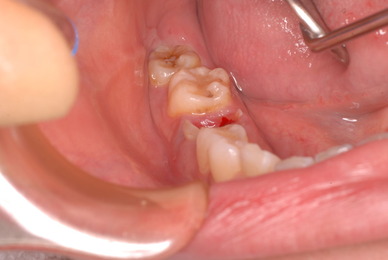

年末の最後の患者さん。

病気の名前を診断もできずにあきらめて、歯科的治療では改善しない事を告げました。

色々な症状を持ち合わせたとしても、歯はいじらない事がよいという事例です。

上記のような方では歯科医師が噛み合わせを変えた為によく噛めないとか常にカチカチ歯がぶつかるというような症状をもっています。でも何もできないのですね。